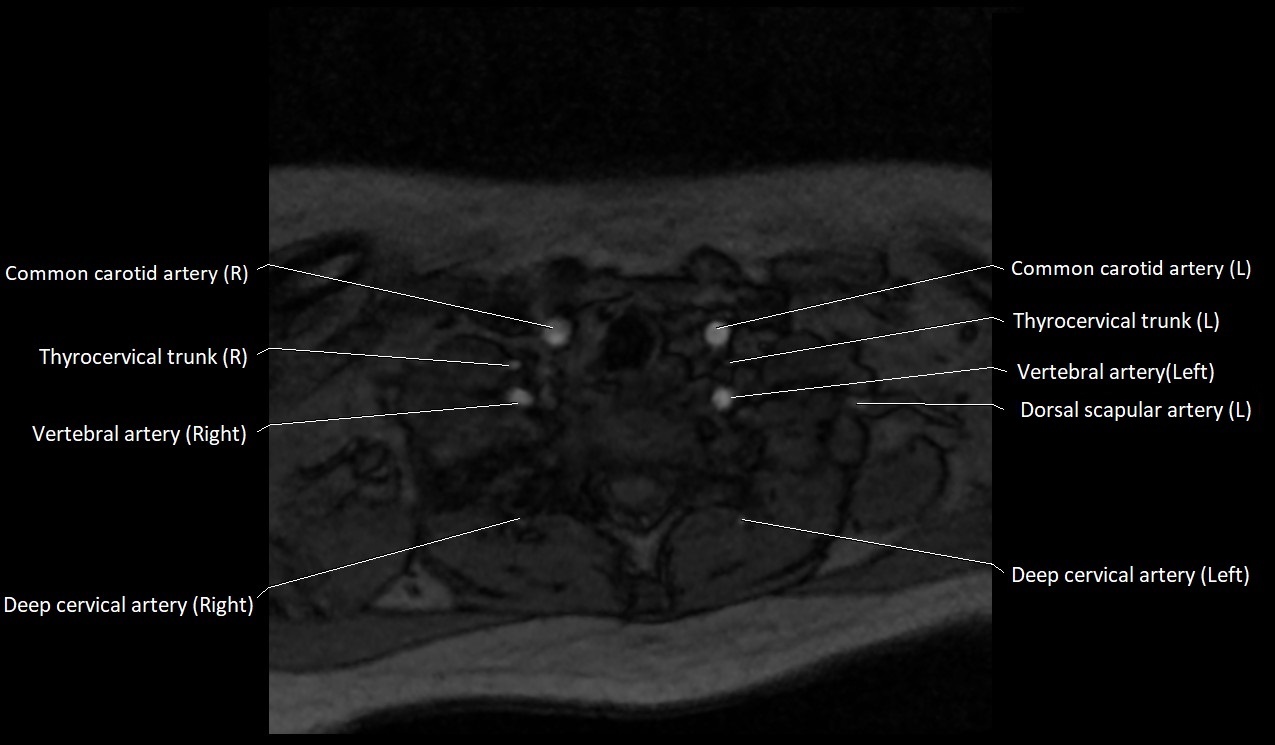

MRI images

image